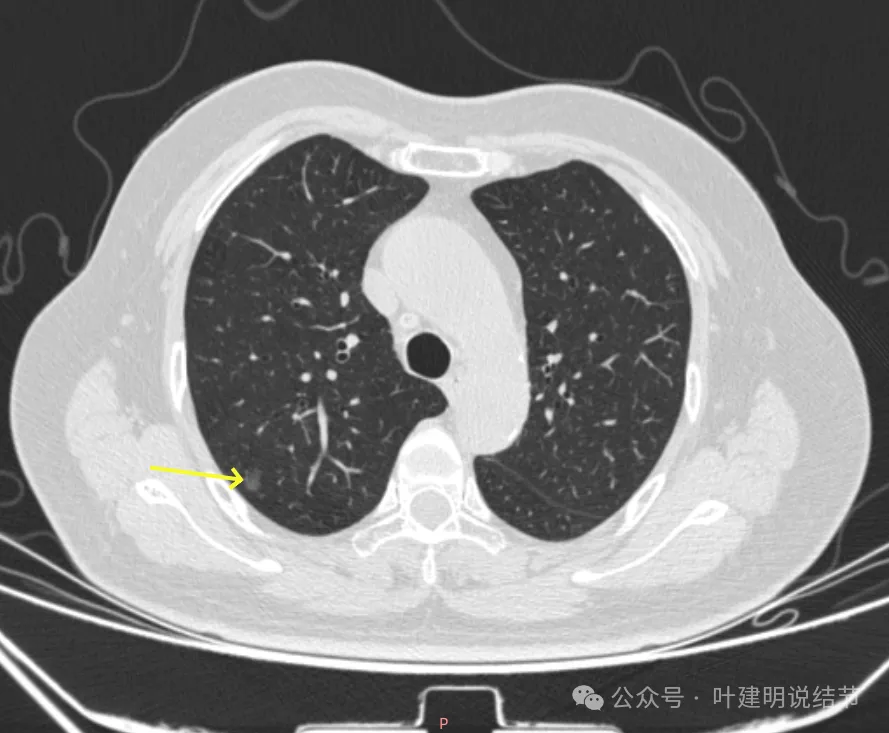

病灶1-4:两肺多处淡磨玻璃结节,密度低,散在,轮廓较清。

病灶10:右侧胸膜下淡磨玻璃结节,轮廓较清。

病灶19-20:两肺淡磨玻璃结节,轮廓较清,小但边界清楚。

病灶23-26:两肺微小淡磨玻璃结节,轮廓较清。

病灶27-30:两肺微小淡磨玻璃结节,轮廓较清。